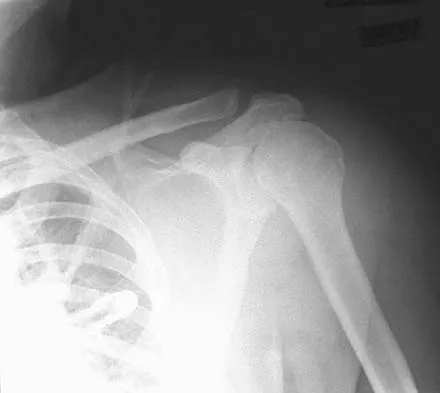

Figure 35 shows the radiograph of a 12-year-old boy who fell off a snowmobile and landed on his left shoulder. He has a closed injury. Management should consist of

Explanation

Proximal humeral fractures in children are classified as metaphyseal or Salter-Harris type I or II fractures, and most of these fractures are treated with closed methods. Eighty percent of the growth of the humerus comes from the proximal physis; therefore, tremendous remodeling potential is present. Indications for open reduction include open fractures or severely displaced fractures in adolescents with minimal growth remaining. Acceptable limits of reduction in adolescent proximal humeral fractures include bayonet apposition and angulation of less than 35 degrees. Common blocks to reduction in adolescents include the biceps tendon and periosteum. For this fracture, use of a shoulder sling without reduction will lead to healing and an excellent result as the proximal humerus remodels. Kohler R, Trillaud JM: Fracture and fracture separation of the proximal humerus in children: Report of 136 cases. J Pediatr Orthop 1983;3:326-332. Beaty JH: Fractures of the proximal humerus and shaft in children. Instr Course Lect 1992;41:369-372. Dobbs MB, Luhmann SL, Gordon JE, et al: Severely displaced proximal humeral epiphyseal fractures. J Pediatr Orthop 2003;23:208-215. Beringer DC, Weiner DS, Noble JS, et al: Severely displaced proximal humeral epiphyseal fractures: A follow-up study. J Pediatr Orthop 1998;18:31-37.